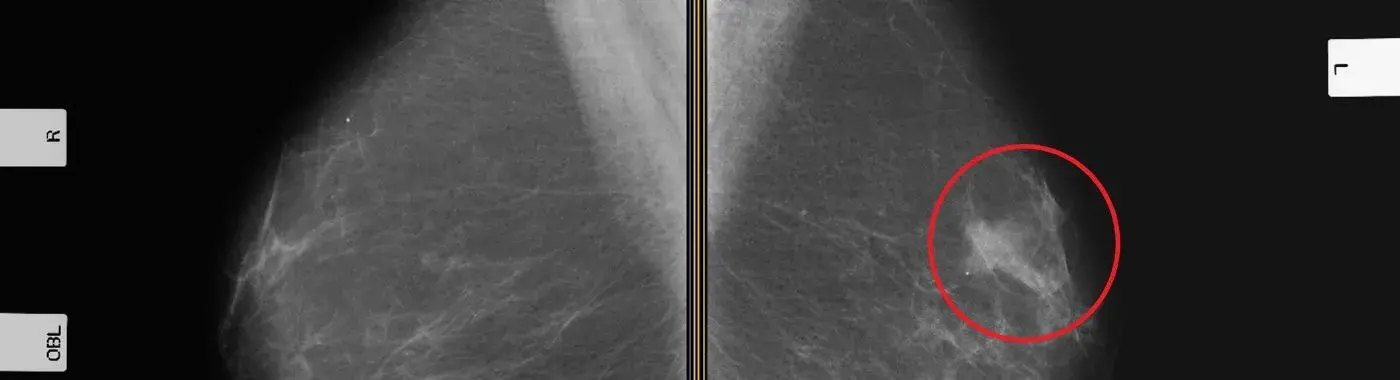

• Mammogram: X-ray images of the breast can detect suspicious growths

• Mammograms: Women aged 40 and older should get regular mammograms, which can spot early signs of cancer, even before it can be felt.